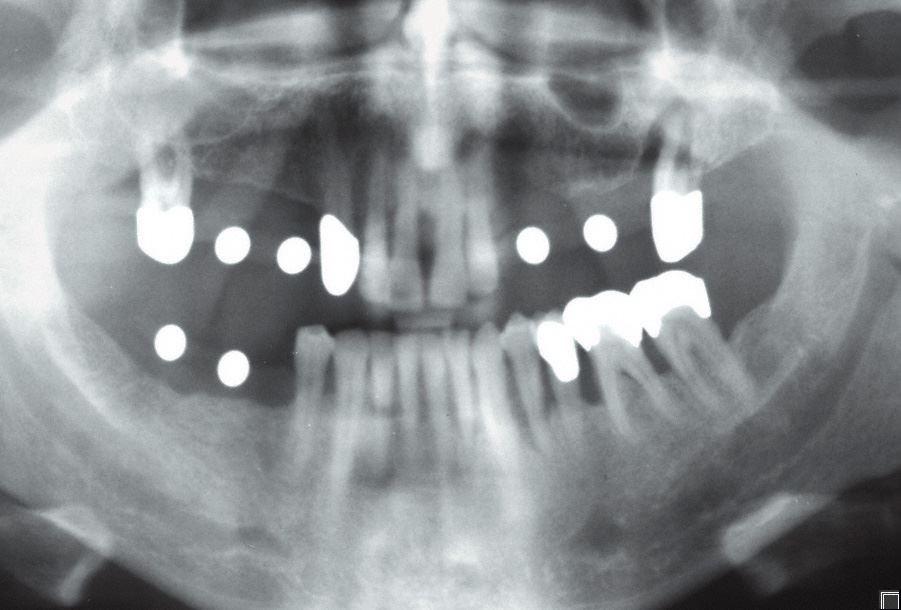

Für ein Implantat werden sowohl eine Mindest-Knochentiefe als auch ein Sicherheitsabstand im Unterkiefer zum Nervenkanal vorausgesetzt. Die Knochentiefe wird durch spezielle Röntgendiagnostik ermittelt.

Mit einer Messkugelschablone können das vertikale Knochenangebot und die mögliche Implantatlänge festgestellt werden.

Die reale Knochenhöhe wird mit Hilfe einer Tiefziehschiene mit eingearbeiteten Metallkugeln ermittelt. Bei digitalen Röntgengeräten kann gegebenenfalls auf die Messaufnahmen verzichtet werden, da sie über ein integriertes Messtool verfügen. Zur Detailabklärung kann es erforderlich sein, zusätzliche Aufnahmen von einzelnen Zahnabschnitten zu machen.

Durch die Computertomographie kann die Lage der später zu setzenden Implantate im Vorfeld schon auf den Millimeter bestimmt werden.